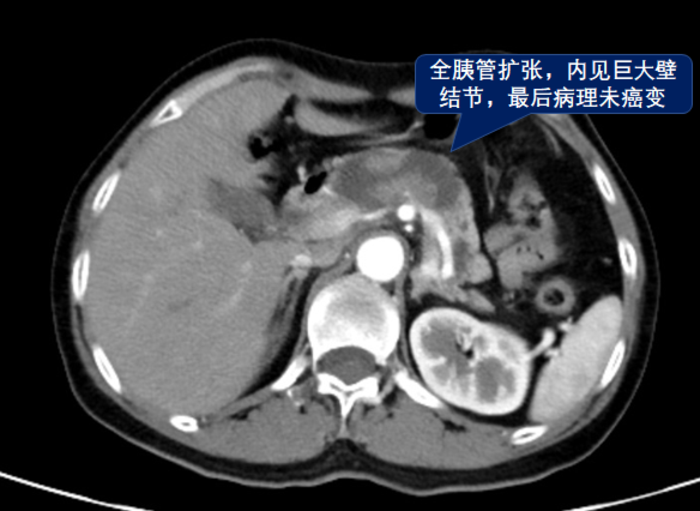

胰腺导管内乳头状黏液性肿瘤(IPMN),是一种具有一定恶变潜能的胰腺囊性肿瘤,分为主胰管型,分支胰管型和混合型。

主胰管型IPMN的主要特征为主胰管呈节段性或弥漫性扩张,扩张的胰管直径往往大于5 mm;分支型IPMN,MRCP可显示病灶与胰管相通,像“提子”一样。主胰管型IPMN的恶变风险大于分支型,反复胰腺炎,主胰管扩张大于10mm,胰管内有附壁结节,胰液细胞学有高度异型细胞,Ca19-9升高等都是高危因素,会建议手术。